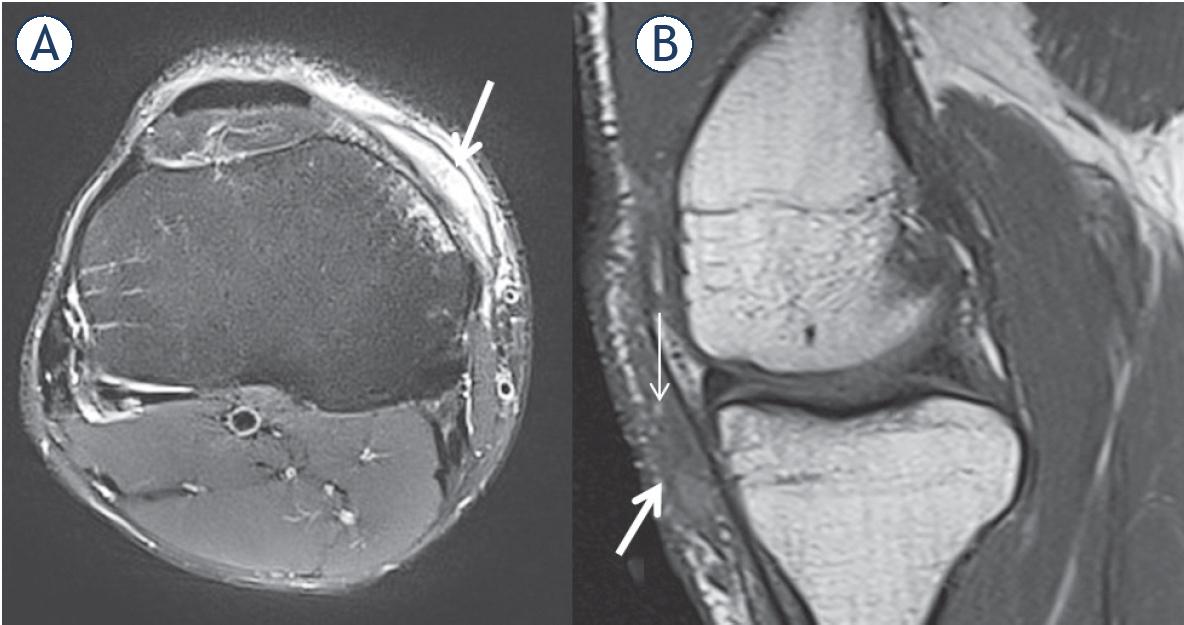

Figure 2